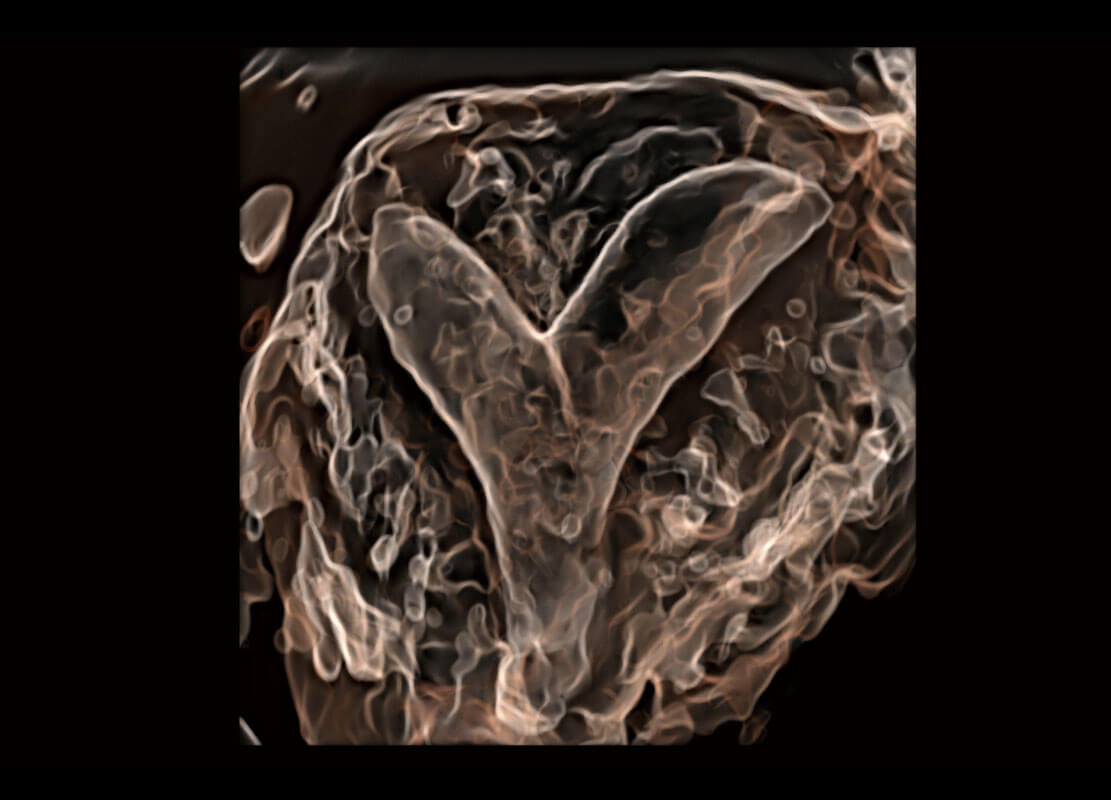

胎心筛查

P60搭载一系列胎儿心脏成像技术,实现更精细的胎儿心脏评估。

• 胎心容积成像